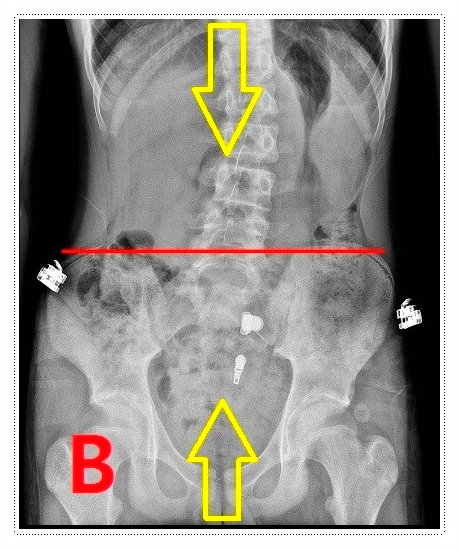

우리가 흔히 떠올리는 척추측만증은 단순히 옆으로 휘는 문제만을 의미하지 않습니다.

척추가 휘어지는 과정에서 골반, 어깨, 목까지 연쇄적으로 영향을 받을 수 있다는 점도 함께 고려해야 하는데요.

Q. 그럼 평발이 척추랑 무슨 상관이 있나요?

평발이 있거나 좌우 발 높이에 차이가 있으면, 그 영향은 무릎과 골반을 거쳐 허리와 척추까지 이어지게 됩니다.